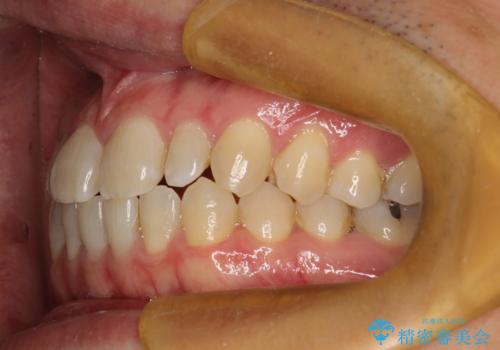

前歯の真ん中の隙間を閉じたい インビザラインによる目立たない矯正

- 上顎の正中の隙間が気になるとのことで来院されました。

下の歯と歯の間をわずかに削り、スペースを作り、正中の隙間を閉じる計画としました。

装置はインビザラインにて行いました。

インビザラインで目立たずに矯正治療を行うことができました。

使用時間を守っていただけたので、比較的スムーズに矯正を終了することができました。